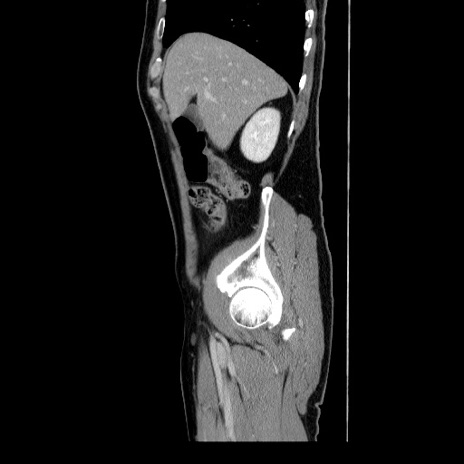

横断像

【症例】60歳代 男性

【主訴】右鼠径部膨隆

【現病歴】1年程前より右鼠径部膨隆あり。自己にて還納可能だったため放置していた。3時間前より右鼠径部の脱出を認め、還納困難となり受診。

【身体所見】右鼠径部に小児頭大の膨隆あり。弾性硬であり、用手還納は困難。左鼠径部にも膨隆を認める。脱出はなし。